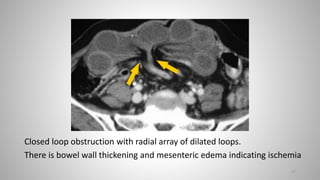

CT

Some or all of the following signs may be demonstrated on CT:

• marked distension of a segment of small bowel

• radially distributed, C or U-shaped small bowel loops

• “Beak sign": of the tapering bowel loops at the point of obstruction

• “Whirl sign": of the tightly twisted mesentery

• two adjacent collapsed loops of bowel

• if strangulation is present, signs of bowel ischaemia (pneumatosis

intestinalis, pneumatosis portalis, pneumoperitoneum)

• “Small bowel feces" sign, with feculent matter mixed with gas bubbles

seen within a dilated segment of small bowel. This results from stasis

and it is present in about 82% of SBOs.

Closed loop obstruction with radial array of dilated loops.

There is bowel wall thickening and mesenteric edema indicating ischemia